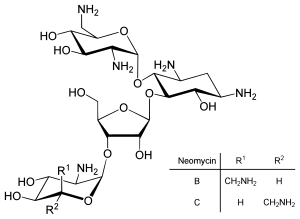

المناطق الغير مترجمة الرئيسية الثلاث والرنا المصغر

تنظيم الترجمة